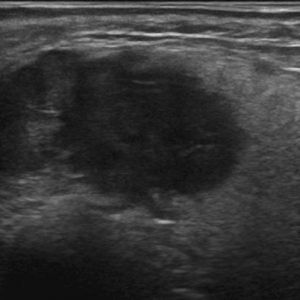

U tuyến nước bọt

Lượt xem: 119» 18-01-2021 -

U tuyến nước bọt

Lượt xem: 152» 18-01-2021 -